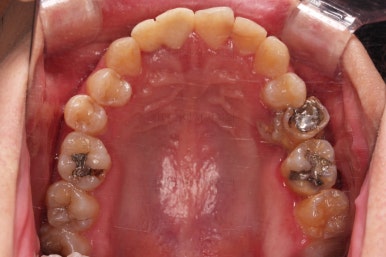

초진 시 입안의 모습입니다.

화살표는 결손 부위, 동그라기믄 유치잔존과 매복치아 부위입니다.

동그라미는 유치가 있는 상황이었는데요. 잇몸도 많이 파괴되어 있었고, 유치 자체의 상태도 좋지 못했어요.